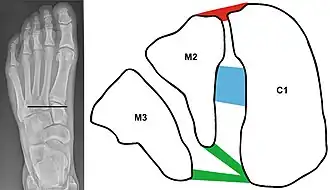

| An X-ray of a Lisfranc injury | |

C1 = Medial cuneiform

M2 = 2nd metatarsal base

M3 = 3rd metatarsal base

Red = dorsal Lisfranc ligament

Blue = interosseous Lisfranc ligament

Green = plantar Lisfranc ligament.

The midfoot consists of five bones that form the arches of the foot (the cuboid, navicular, and three cuneiform bones) and their articulations with the bases of the five metatarsal bones. It is these articulations that are damaged in a Lisfranc injury. Such injuries typically involve the ligaments between the medial cuneiform bone and the bases of the second and third metatarsal bones, and each of these ligaments is called Lisfranc ligament.[4]